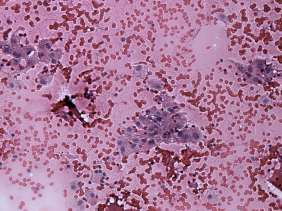

Cytology was performed from one of the moderately hypoechogenic lesions. It was located next lateral to the echonormal lesion. There were two cell populations on the smear: beside regular thyrocytes, follicular cells presenting oxyphilic metaplasia were also found on the smear.

The possibility of an oxyphilic tumor could not be fully excluded solely on cytology.

Taking the ultrasound presentation into account, the risk of oxyphilic tumor was even lower because the ultrasound pattern corresponds either to hyperplastic nodules or to an autoimmune thyroiditis.